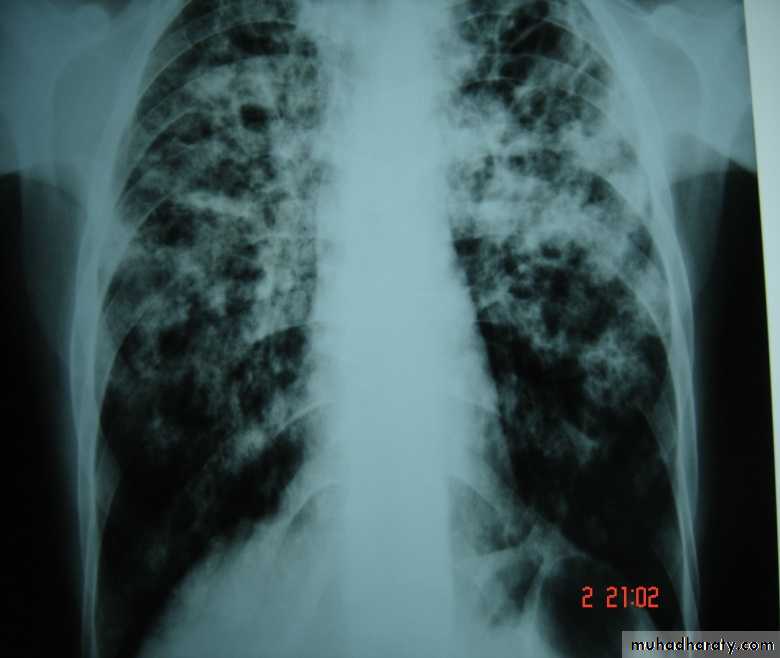

• Bronchiectasis

• Is a persistent abnormal dilatation of the bronchi generally beyond the sub segmental level , generally classified as three types cylindrical , varicose & saccular . The left lower lobe is more commonly involved then the right lower lobe .• Aetiology :-

• It includes (Bronchiectasis , situs inversus ,sinusitis ,sperms hypo motility ) .It represents genetic disorder with abnormal ciliary motility so impaired clearance of sputum with the resultant bronchiectasis .• Clinical manifestation :-The onset is mostly in childhood whereas symptoms generally appear in the second or third decade of life .The disease is more common in females .Major symptom cough with the production of purulent sputum with fetor oris .50% of the patients presented with haemoptysis .Others present with repeated RT infection .,others develop osteo arthropathy & finger clubbing which will resolve with treatment .

• Diagnosis :-

• 1-History chronic cough with purulent sputum.

• 2-Plain CXR may shows prominent vascular marking .

• 3-Bronchoscopy to diagnose obstructive lesion & to obtain bronchial wash for C&S test .

• 4-Bronchography through giving radio opaque dye through the bronchoscope & into bronchial tree ,now replaced completely by CT.

• 5-Chest CT is the single non invasive tool for both diagnosing &assessing the severity of the disease .